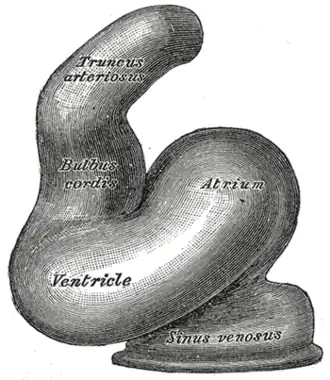

Heart of human embryo of about twenty-four days. (Truncus arteriosus visible at top.) | |

The truncus arteriosus is a structure that is present during embryonic development. It is an arterial trunk that originates from both ventricles of the heart that later divides into the aorta and the pulmonary trunk.[1]

Structure

The truncus arteriosus and bulbus cordis are divided by the aorticopulmonary septum. The truncus arteriosus gives rise to the ascending aorta and the pulmonary trunk. The caudal end of the bulbus cordis gives rise to the smooth parts (outflow tract) of the left and right ventricles (aortic vestibule & conus arteriosus respectively).[2] The cranial end of the bulbus cordis (also known as the conus cordis) gives rise to the aorta and pulmonary trunk with the truncus arteriosus.